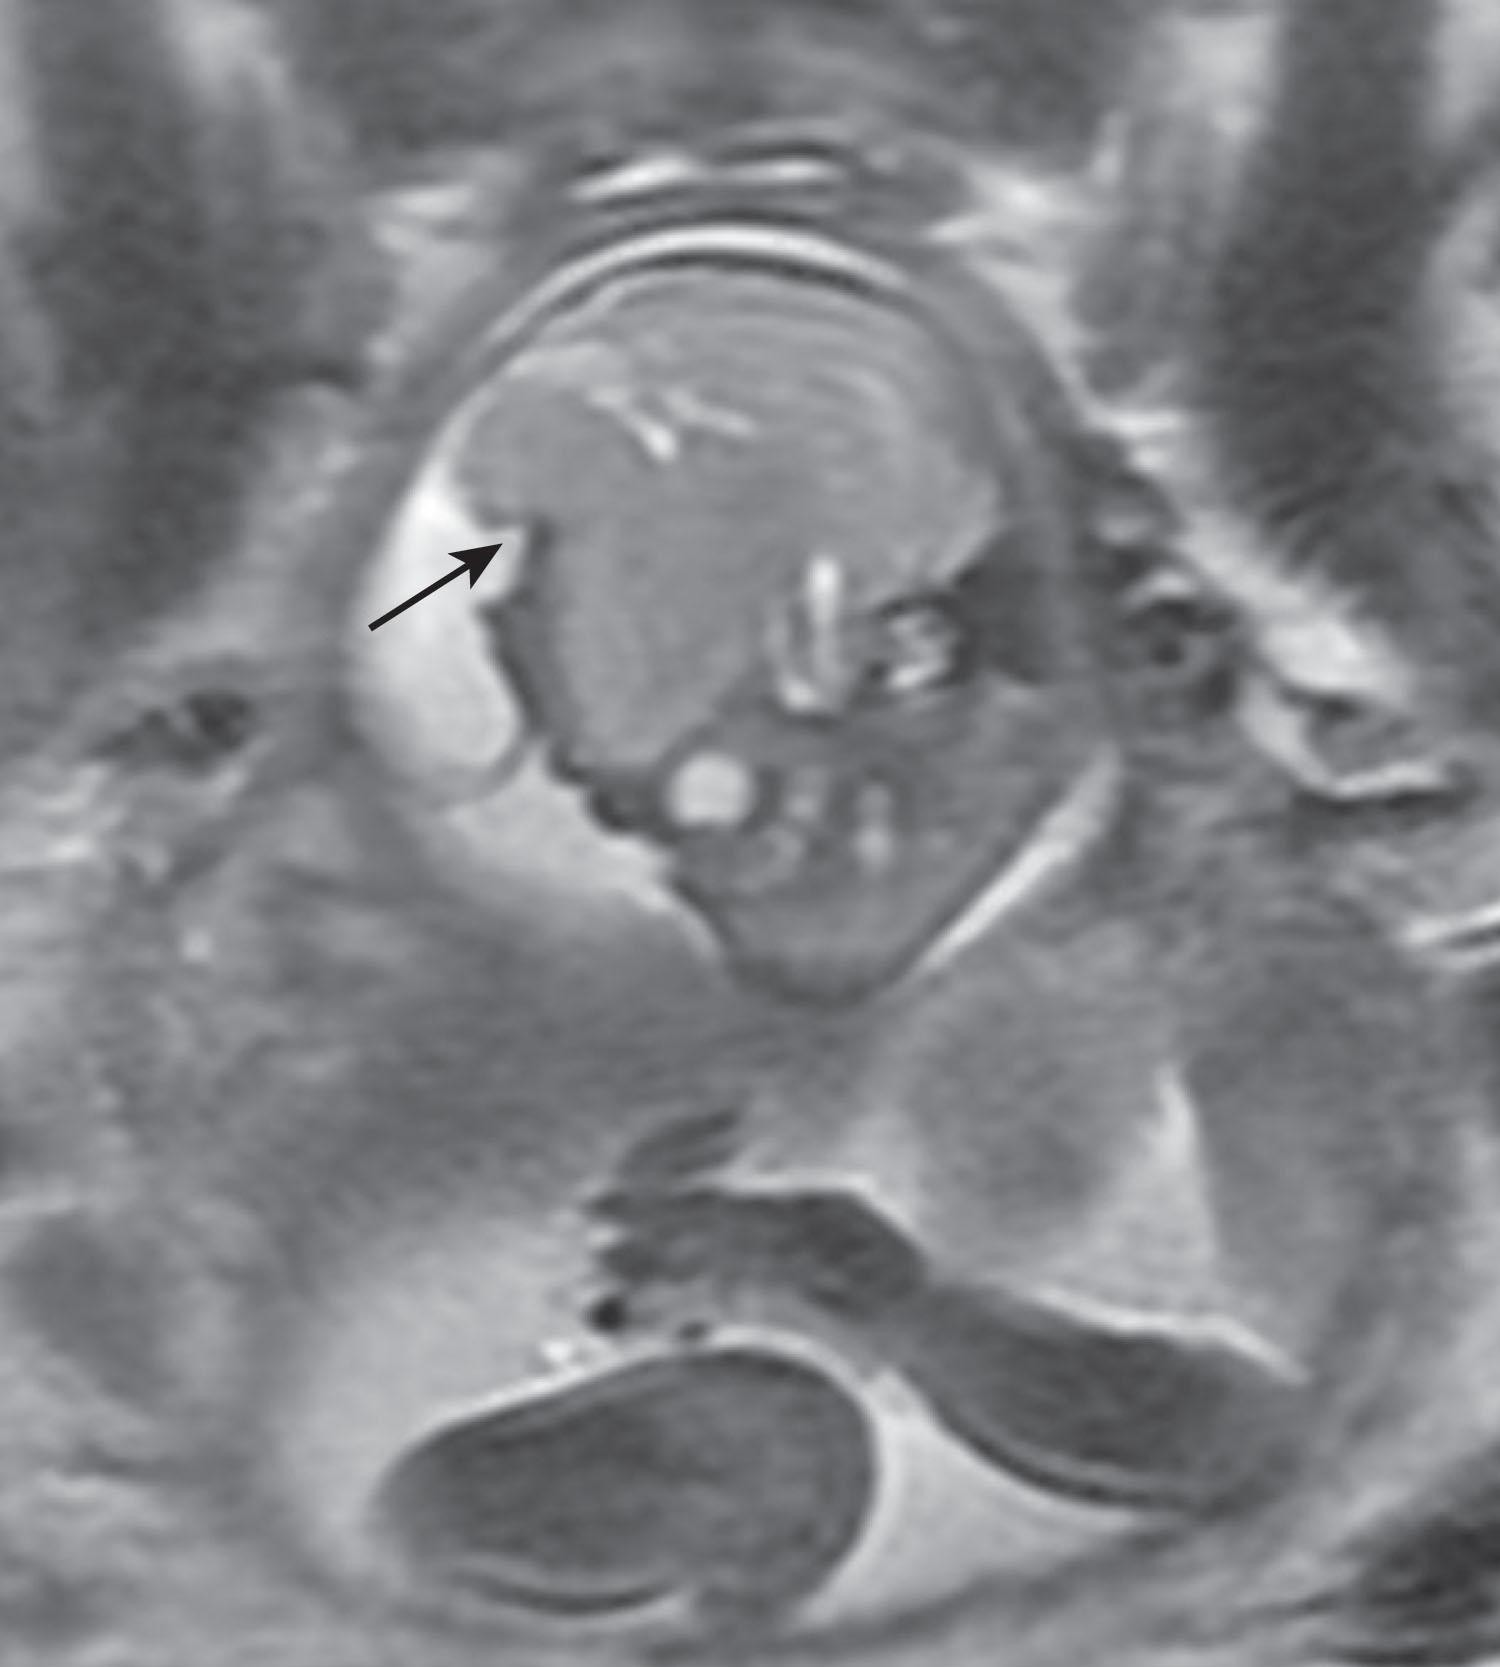

Encephaloceles (see Box 1.3 ) were previously considered a restricted disorder of neurulation involving anterior neural tube closure , although the precise pathogenesis of these lesions remains unknown. It may be better to consider these lesions as developmental disorders of cranial mesoderm in which the cranial defect is associated with a cystic extracranial extension of meninges, neural tissue, and CSF. The notion that encephaloceles are not disorders of primary neurulation is supported by the fact that the herniated brain parenchyma is relatively normal and shows no evidence of defective neurulation. Many encephaloceles are skin-covered—that is, closed—lesions. When the cystic lesion includes parts of the ventricular system, the term meningoencephalocystocele is used ( Fig. 1.5 ). Lesions that involve primarily or only the overlying meninges or skull, without obvious inclusion of neural elements, are called cranial meningoceles ( Fig. 1.6 ); these are thought to be later in onset and account for up to 20% of cystic occipital lesions. Encephaloceles occur most commonly (70% to 80%) in the occipital region ( Fig. 1.7 ), less commonly in the frontal ( Fig. 1.8 ) and frontoparietal regions ( Fig. 1.9 ), and least commonly in the temporal and parietal regions. Frontal encephaloceles may protrude into the nasal cavity (fronto-ethmoidal encephaloceles; Fig. 1.10 ). Fronto-ethmoidal encephaloceles may be due to disturbed separation (nondisjunction) of the neural ectoderm from the cutaneous ectoderm during final closure of the rostral neuropore. In the typical occipital encephalocele, the protruding brain is usually derived from the occipital lobe and may be accompanied by dysraphic disturbances involving cerebellum and superior mesencephalon. The neural tissue in an encephalocele usually connects to the underlying CNS through a narrow neck of tissue. The protruding mass is usually represented by a closed neural tube with cerebral cortex, exhibiting a normal gyral pattern, and subcortical white matter. As many as 50% of cases are complicated by hydrocephalus. Encephaloceles located in the low occipital (below the inion) or high cervical regions and combined with deformities of lower brainstem and of base of skull and upper cervical vertebrae characteristic of the Chiari type II malformation (associated with myelomeningocele [see later]) comprise the Chiari type III malformation. This type of encephalocele contains cerebellum in virtually all cases and occipital lobes in approximately one half of cases ( Fig. 1.11 ). Partial or complete agenesis of the corpus callosum occurs in two-thirds of cases. Venous structures may be included in the cyst, and anomalous venous drainage (aberrant sinuses and deep veins) is present in about one-half of patients and may complicate the surgical approach to these lesions.

Fig. 1.9, Frontoparietal encephalocele. Fetal MRI (T2-weighted) angled sagittal view showing herniation of brain parenchyma through cranial defect ( arrow ).